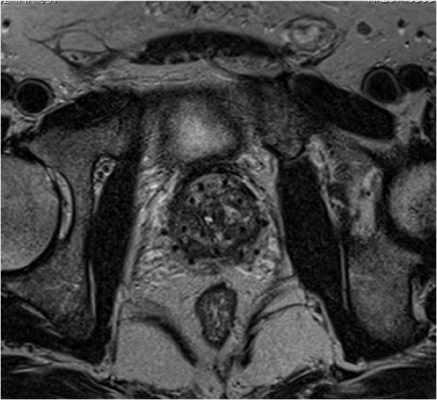

The study examined the patient-reported outcomes of 91 men with prostate cancer who received magnetic resonance imaging (MRI)-guided, vessel-sparing radiation at University of Michigan Providence Cancer Institute. The vessel-sparing radiation technique limits the amount of radiation to critical erectile tissues using MRI scans to identify the blood vessels responsible for erections. When radiation dose is limited to these critical structures, the risk of erectile dysfunction is lowered.

Of the 91 patients studied, all patients received EBRT. Forty-two of the patients received only EBRT (>77.8Gy), and 49 patients received EBRT plus brachytherapy, the implantation of radioactive seeds near the prostate. The combination patients received brachytherapy in the form of an I-125 permanent prostate implant. None of the patients received androgen deprivation therapy (ADT).